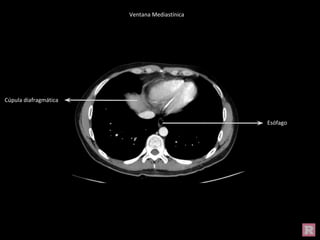

Ventana Mediastínica

Cúpula diafragmática

Esófago